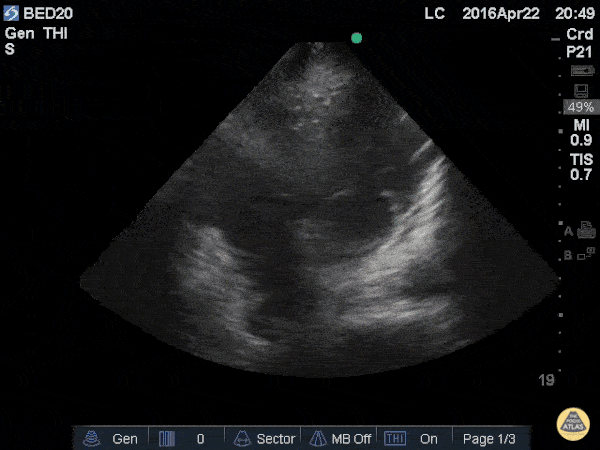

The included clip demonstrates an apical 4 chamber view with saline bubbles in the right atrium and right ventricle after a quick 10ml flush through a right IJ central line. 56 y/o M with pneumonia, respiratory distress, intubated, and hemodynamically unstable was started or levophed through a peripheral IV while a right IN was started. The portable x-ray tech wa missing but rapidly flushing saline through the IJ during apical 4 clearly demonstrates saline the R circulation After placing central lines, confirmation by chest x-ray is not always available. When the patient is unstable, delayed use can be consequential. Visualizing the saline swirling in the right side of the heart immediately after a flush is highly predictive of proper catheter tip placement. Weekes AJ et al. Central vascular catheter placement evaluation using saline flush and bedside echocardiography. Acad Emerg Med. 2014 Jan;21(1):65-72. doi: 10.1111/acem.12283. Leon Chen, NP – Critical Care Medicine Service; Department of Anesthesiology and Critical Care Medicine; Memorial Sloan Kettering Cancer Center; New York, NY